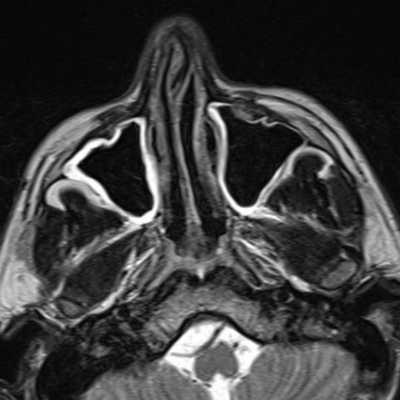

Магнитно-резонансная томография

МРТ придаточных пазух особенно важна в диагностике осложнений, особенно, распространения инфекции в полость черепа.

Стандартное исследование предполагает корональные Т1- и Т2-зависимые МРТ

изображения. Подавление сигнала от жира рекомендуется, но не является обязательным. Необходимость других проекций и импульсных последовательностей диктуется конкретной клинической ситуацией. При подозрении на опухоль рекомендуется исследование с контрастированием.

Жидкость, ретенционные кисты и отёчная слизистая гиперинтенсивны на Т2-зависимых МРТ изображениях. Т1-зависимые МРТ изображения иногда вносят ясность, так как ретенционные кисты могут быть светлее за счет повышенного содержания белка. Жидкость, напротив, обычно темнее воспаленной слизистой.

Главным недостатком МРТ является плохая визуализация костных границ синусов. Кроме того, отмечается высокий уровень ложно-положительных результатов. Небольшой гиперинтенсивных сигнал от слизистой на Т2-зависимых томограммах при отсутствии клинической симптоматики наблюдается часто у здоровых лиц. Таким образом, при неосложненных острых синуситах МРТ не является обязательной диагностической процедурой.

Этмоидит. МРТ придаточных пазух носа. Поперечная плоскость (увеличение), Т1-зависимое МРТ изображение.